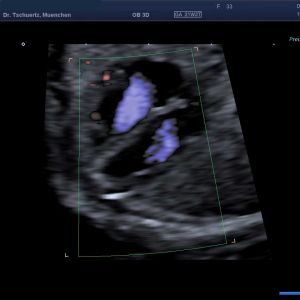

Fetale Echokardiographie – differenzierter Herzultraschall

Die Häufigkeit von angeborenen Herzfehlern beim Neugeborenen beträgt etwa 1%.

Schwerwiegende komplexe Herzfehler können schon im 1. Trimenon im Rahmen der frühen Fehlbildungsdiagnostik erfasst werden – optimaler Zeitpunkt zur Diagnostik von Herzfehlern ist die 20. - 22. SSW in Rahmen der Feindiagnostik (Organultraschall). Beurteilt werden die Lage des Herzens, die Herzkammern, die Herzklappen, die dem Herzen entspringenden Gefäße und der Herzrhythmus.

Viele Herzfehler treten in Verbindung mit Chromosomenstörungen oder syndromalen Erkrankungen auf. Wird pränatal ein Herzfehler festgestellt, bieten wir eine diagnostische Punktion zur weiterführenden genetischen Abklärung an.